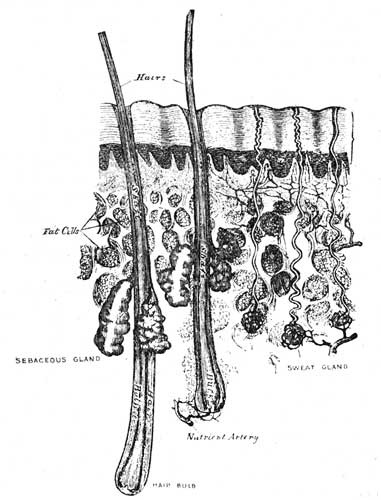

Fig. 1.—A bit of the inner coat of the small intestine.

Fine threads of blood vessels (capillaries) take it up from the stomach and intestines. Also along the intestines there are little projections (villi), through which the food passes into a blood stream leading to the liver, where the blood is then purified. These projections also contain lacteals or little vessels containing blood without its red corpuscles. A duct carries this colourless blood mixed with absorbed food to the left side of the neck, where it empties into the blood stream. These lacteals have a special affinity for the fat of the food. Most of the rest of the food, including the proteid and the carbohydrate or starchy portion now in the form of sugar, passes into the capillaries, and then is led to the liver.

The liver will not let through more sugar than is required, storing it up for future use. It also acts as a careful guardian, by arresting many poisons which would otherwise pass into the general circulation. The liver requires for the proper performance of its functions plenty of pure blood, hence the necessity for fresh air and exercise, that the lungs may work well. The liver is easily influenced by alcoholic beverages, and by getting too hard work to do through eating rich foods. A consideration of this delicate and intricate process, whereby the digested food is absorbed, will show that badly-digested food can not hope to be well assimilated, consequently attention should be paid to the quantity and quality of the food we eat (see Digestion; Diet).

Fig. 2.—Two villi containing lacteals. The white canals are lacteals, the darker lines indicate blood vessels (capillaries). Magnified 100 diameters.

(From "Quain's Anatomy.")

Whatever thus makes living substance is nourishment; whatever fails to do so is not. If food be taken, and even digested, without being thus assimilated, it becomes an injury to a patient instead of a help. In cases of fever, inflammatory disease, or wasting sores, much rich food feeds the fire. It is like laying rafters on the roof of a burning house for purposes of repair. In such a case small quantities of milk, or milk and hot water (see Digestion), represent the total food which can be effectively used in the body. We write on this subject that in treatment our friends may watch not to injure by making the blood too rich in elements which the system cannot usefully assimilate. Such foods as oatmeal jelly and wheaten porridge will often furnish more real nourishment than pounds of bread, beef, and potatoes. A little careful thought will guide to correct treatment in this matter. An easily assimilated diet is found in Saltcoats biscuits and hot water; many inveterate stomach troubles have yielded to this, when taken as sole diet for some weeks (see Biscuits and Water).